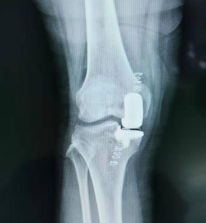

术后x光片

术团队术中在右前膝内侧小心切开,显露关节后,发现内侧关节软骨磨损严重,骨质增生,在清理好骨赘之后,对胫骨内侧进行修补,在测试过屈伸活动正常后,手术顺利结束。

同一般的全膝关节表面置换术相比,它具有切口小、切除骨质少、植入物少、手术时间短、并发症少、术后恢复快、关节活动范围更大、运动功能保留更好的优点。